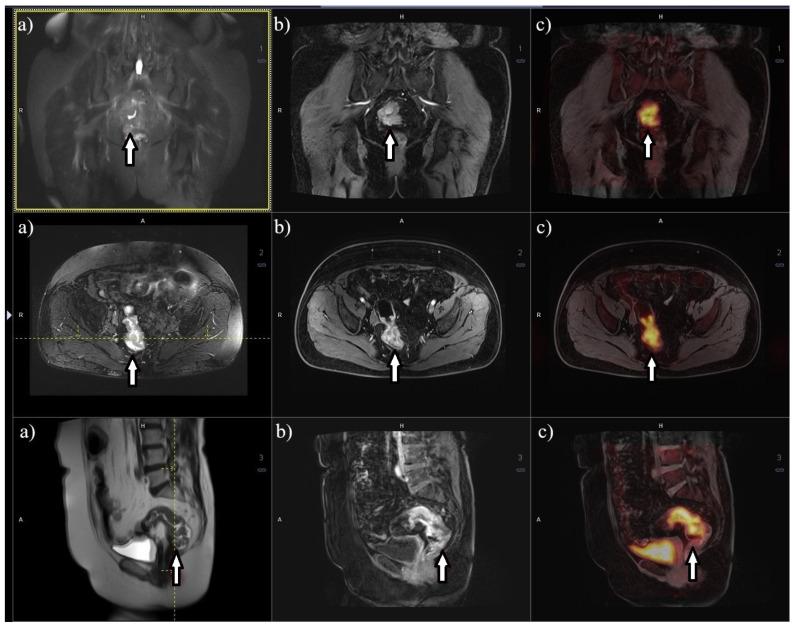

Rectal cancer (RC) is a prevalent malignancy with significant morbidity and mortality rates. The accurate staging of RC is crucial for optimal treatment planning and patient outcomes. This review aims to summarize the current literature on imaging and metabolic diagnostic methods used in the stage assessment of RC. Various imaging modalities play a pivotal role in the initial evaluation and staging of RC. These include magnetic resonance imaging (MRI), computed tomography (CT), and endorectal ultrasound (ERUS). MRI has emerged as the gold standard for local staging due to its superior soft tissue resolution and ability to assess tumor invasion depth, lymph node involvement, and the presence of extramural vascular invasion. CT imaging provides valuable information about distant metastases and helps determine the feasibility of surgical resection. ERUS aids in assessing tumor depth, perirectal lymph nodes, and sphincter involvement. Understanding the strengths and limitations of each diagnostic modality is essential for accurate staging and treatment decisions in RC. Furthermore, the integration of multiple imaging and metabolic methods, such as PET/CT or PET/MRI, can enhance diagnostic accuracy and provide valuable prognostic information. Thus, a literature review was conducted to investigate and assess the effectiveness and accuracy of diagnostic methods, both imaging and metabolic, in the stage assessment of RC.

直肠癌(RC)是一种常见的恶性肿瘤,发病率和死亡率都很高。准确的直肠癌分期对于优化治疗方案和患者预后至关重要。本综述旨在总结目前关于直肠癌分期评估中使用的影像学和代谢诊断方法的文献。各种影像学检查在直肠癌的初始评估和分期中起着关键作用。这些检查包括磁共振成像(MRI)、计算机断层扫描(CT)和直肠内超声(ERUS)。由于MRI具有卓越的软组织分辨率以及评估肿瘤浸润深度、淋巴结受累情况和壁外血管侵犯的能力,它已成为局部分期的金标准。CT成像提供了有关远处转移的有价值信息,并有助于确定手术切除的可行性。ERUS有助于评估肿瘤深度、直肠周围淋巴结和括约肌受累情况。了解每种诊断方法的优缺点对于直肠癌的准确分期和治疗决策至关重要。此外,整合多种影像学和代谢方法,如PET/CT或PET/MRI,可以提高诊断准确性并提供有价值的预后信息。因此,我们进行了一项文献综述,以研究和评估影像学和代谢诊断方法在直肠癌分期评估中的有效性和准确性。